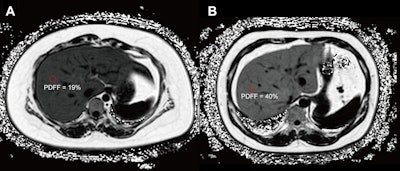

Axial proton density fat fraction (PDFF) maps show hepatic steatosis assessment in patients with dysglycemia. (A) PDFF map in a 27-year-old female patient (body mass index [BMI; calculated as weight in kilograms divided by height in meters squared] = 38.9) with a 1-year history of obesity and metabolic syndrome, and hospital-confirmed prediabetes. The image shows moderate hepatic steatosis (mean liver PDFF, 19%; circle). (B) PDFF map in a 40-year-old male patient (BMI = 33.35) with a history of obesity, metabolic syndrome, hypertension, and hospital-confirmed type II diabetes. The image shows severe hepatic steatosis (mean liver PDFF, 40%; circle). RSNA